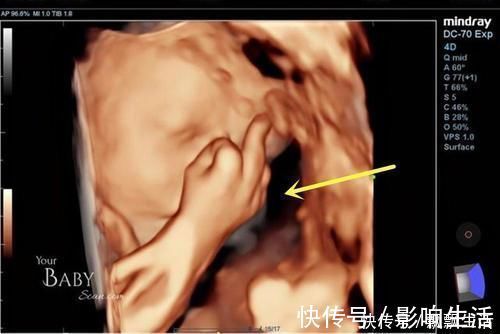

英国孕38周孕妈做彩超,宝宝在肚子里各种搞怪!?

英国的一位孕妈在怀孕38周时去做彩超,在显像下看到了宝宝的可爱样子,宝宝一会儿自己竖中指玩,一会儿又打哈欠,挡着脸玩起来了“捉迷藏”……

文章插图

由于这是他们的第一个宝宝,看到宝宝的这些神奇举动很兴奋,而且明显的看得出,胎儿已经是个“小宝宝”的样子了,而且在妈妈肚子里还很淘气。